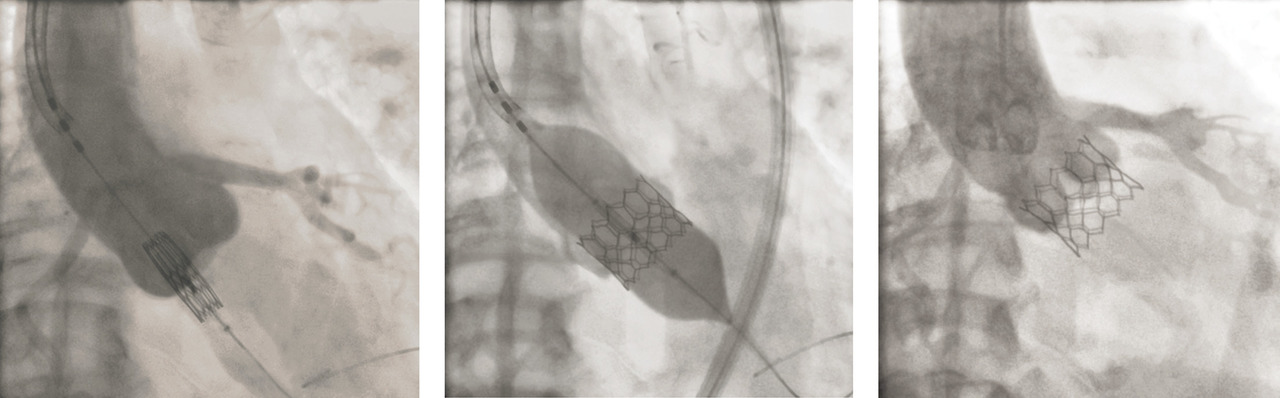

En 2002, le Pr Alain Cribier réalise à Rouen la première implantation par voie percutanée d’une valve biologique aortique (transcatheter aortic valve intervention [TAVI]). Proposée au début aux patients ayant des contre-indications absolues à la chirurgie, cette nouvelle technique a rapidement évolué et est désormais standardisée. Dans le modèle développé par Alain Cribier, une valve biologique est cousue dans une endoprothèse qui est sertie sur un ballon fixé à l’extrémité d’un cathéter (fig. 1 ). Le cathéter est monté le plus souvent par l’artère fémorale et l’ensemble ballon-endoprothèse est positionné au niveau de la valve aortique. Le ballon est ensuite gonflé brièvement puis retiré, permettant l’expansion de l’endoprothèse et le déploiement de la valve biologique (fig. 2 ).

En 2002, le Pr Alain Cribier réalise à Rouen la première implantation par voie percutanée d’une valve biologique aortique (transcatheter aortic valve intervention [TAVI]). Proposée au début aux patients ayant des contre-indications absolues à la chirurgie, cette nouvelle technique a rapidement évolué et est désormais standardisée. Dans le modèle développé par Alain Cribier, une valve biologique est cousue dans une endoprothèse qui est sertie sur un ballon fixé à l’extrémité d’un cathéter (